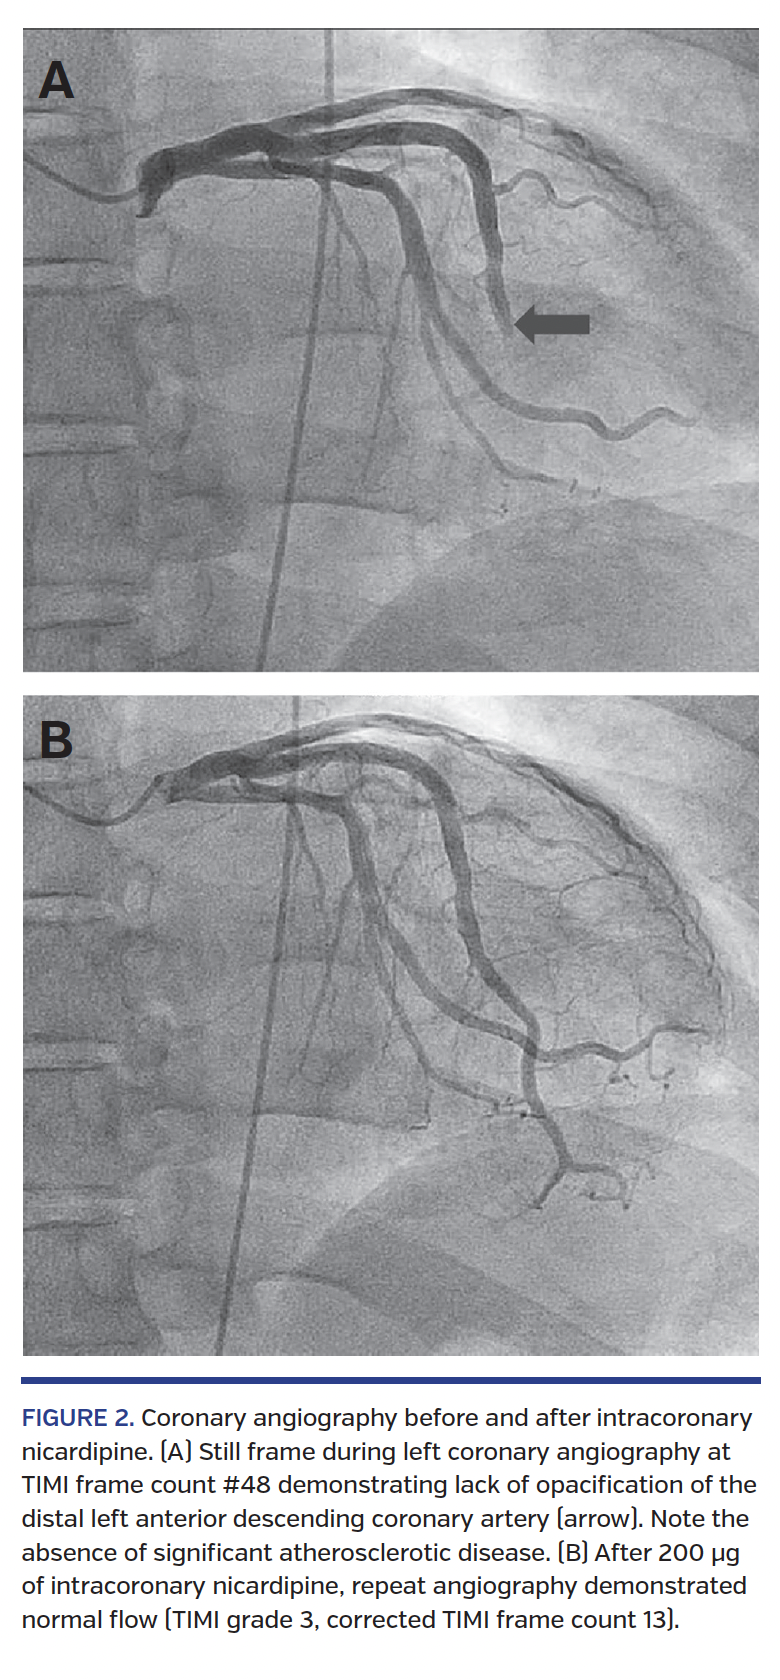

IC nicardipine characteristically resulted in markedly accelerated angiographic filling of the coronary arteries (Figure 2; Video 1); this observation was corroborated by TIMI flow and TFC analysis. In vessels with CSF, TFC improved from 47 ± 17 at baseline to 15 ± 5 after IC nicardipine administration (P<.001) (Figure 3). All vessels demonstrated TIMI 3 flow and TFC <28 following nicardipine. Significant improvement in TFC was seen for all vascular territories (Figure 4). No adverse effects were observed with drug administration.